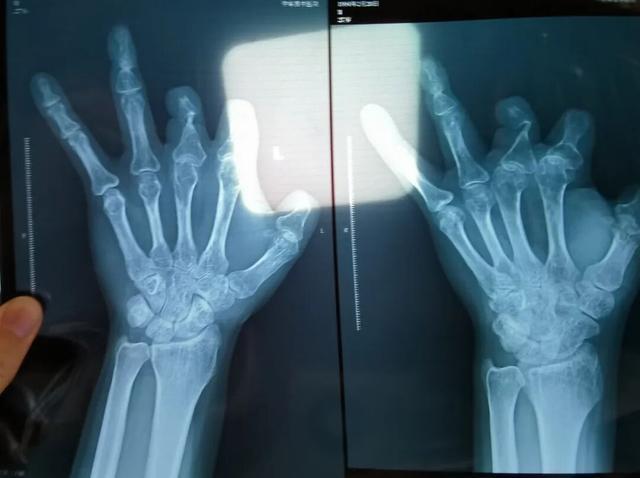

患者王海森左手拇指关节以上部位被电锯切断,收费单显示术中使用了微血管吻合装置,但X光片中未显示该器械。新京报记者 程亚龙 摄

单价1.68万元,声称在术中植入体内、用于缝合血管的两个环形吻合装置,竟然在王海森的X光片上消失了。

彭先生称,因为他的手术并不成功,术后他委托律师欲将郑大一附院诉至法庭。在律师的指导下,他到医院拍摄了X光片,偶然发现术中使用的6个吻合装置,都“消失”在了血管内。

该产品的代理商曾向新京报记者证实,微血管吻合装置为植入型医疗器材,患者拍摄X光片时会有显示。新京报记者获取了一位曾在郑大一附院接受手术、使用了该产品的患者的X光片,其手术部位可见一绿豆大小的光圈。

装置上带有不锈钢针,不可能被人体吸收,唯一的可能就是“手术时其实没有使用”。尽管之前也有其他人向王海森透露过这一点,但直到看到片子前,他一直都不相信。